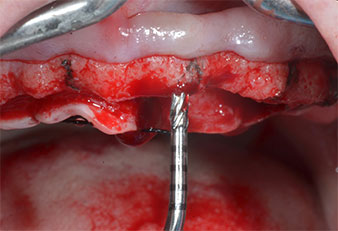

Ein flammenförmiges, diamantiertes piezochirurgisches Instrument (Piezomed I1) wurde verwendet, um die Implantatpositionen zu markieren und die Pilotpräparationen durchzuführen (Abb. 3). Dabei wurde darauf geachtet, eine Auf- und Abbewegung mit reduzierter Leistung, voller Spülung und niedrigem Druck (unter 300 g) anzuwenden. Als Nächstes wurde ein Pilotinstrument (Piezomed I2A/I2P) zur initialen Erweiterung der Implantatlager auf einen Durchmesser von 2 mm verwendet (Abb. 4), gefolgt von einem 3-mm-Instrument (Abb. 5).

Im vorliegenden Fall wurden die Instrumente Z25P und Z35P wegen des relativ weichen posterioren Knochens nicht verwendet, der problemlos mit dem I3A/I3P bearbeitet werden konnte.

Wegen des relativ harten Knochens (D2) an den Positionen 11 und 21 wurden die 10 mm langen Implantatlager in diesem Bereich abschließend mit einem 4-mm-Spiralbohrer, dem chirurgischen Winkelstück WS-75 L von W&H und dem W&H Implantmed Implantologiemotor in Verbindung mit dem optionalen W&H Osstell ISQ module präpariert. Im Gegensatz dazu wurde der weiche Knochen der Implantatlager im Seitenzahnbereich mit dem Piezomed I3P auf den abschließenden Durchmesser von 3 mm erweitert. Die Implantate wurden dann transgingival eingesetzt, die Einheildauer betrug drei Monate (Abb. 6-10). Die vorhandene Prothese wurde auf vier provisorischen Implantaten abgestützt (Abb. 8).